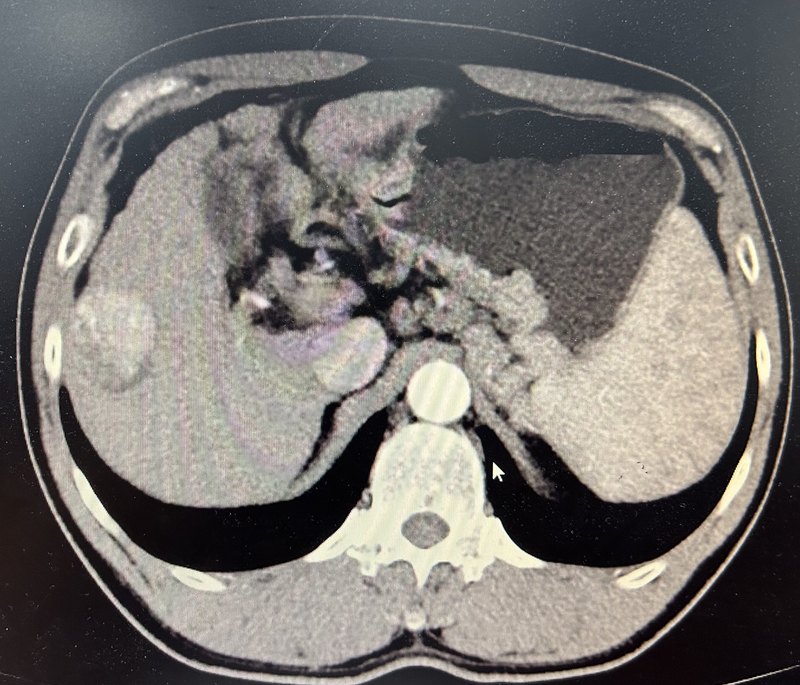

患者老年男性,乙肝肝硬化脾亢門脈高壓多年,近期發(fā)現(xiàn)肝癌。ct可見右肝癌并門脈高壓。造影右肝可見腫瘤染色,脾動脈稍增粗。行tace及脾動脈主干彈簧圈栓塞后再次造影右肝腫瘤未見染色,脾動脈遠端血流減少。行脾微波消融糾正脾亢。行肝癌微波消融治療。右肝腫瘤完全滅活,脾臟可見片狀壞死灶,脾臟明顯縮小。再次造影右肝腫瘤未見染色,脾動脈中段部分閉塞,脾臟血流減少。點評:對于小肝癌合并門脈高壓脾功能亢進,我們推薦采取脾動脈主干彈簧圈栓塞限流降低門脈壓力,聯(lián)合內鏡下套扎避免消化道出血,然后行脾微波消融糾正脾功能亢進,同時tace聯(lián)合微波消融滅活肝腫瘤的方案,同時治療肝癌及門脈高壓,相信這個方案未來會被主流接納成為首選方案。